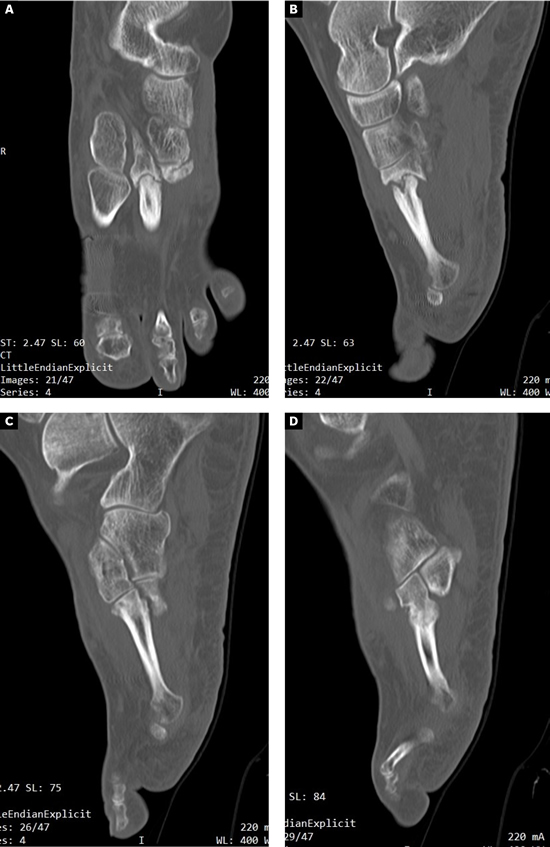

Se realizó radiografía dorso-plantar en carga del pie derecho (Figura 1) que mostraba una imagen radiológica compatible con ausencia de consolidación de las osteotomías en las bases de 2.º, 3.º y 4.º metatarsianos, además de la presencia de hallux abductus valgus. Se solicitó una tomografía axial computarizada (TAC) para estudiar más detenidamente el estado actual del proceso de consolidación ósea. La paciente acudió con resultado de TAC el 5 de mayo de 2015, donde se evidenció la ausencia completa de consolidación ósea en segundo metatarsiano (Figuras 2A y 2B), consolidación prácticamente completa de tercer metatarsiano (Figura 2C) y la presencia de callo óseo con consolidación incompleta en el cuatro metatarsiano (Figura 2D).

Figura 1. Radiografía dorso-plantar en carga del pie derecho. Se evidencia la ausencia de consolidación de las osteotomías en las bases de 2.º, 3.º y 4.º metatarsianos después de 9 meses de la intervención inicial.

Figura 2. Radiografía dorso-plantar en carga del pie derecho. Se evidencia la ausencia de consolidación de las osteotomías en las bases de 2.º, 3.º y 4.º metatarsianos después de 9 meses de la intervención inicial.